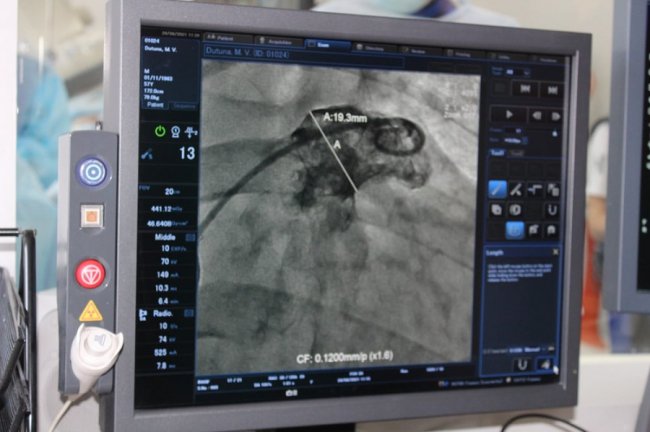

Пацієнтам імплантовано спеціальний пристрій - оклюдер останнього покоління UltraSept LAA виробництва CARDIA (USA).

Обидві операції пройшли успішно. Їх проводили за допомогою ангіографа (із застосуванням рентгенологічного обладнання) через прокол у судині на нозі і не потребували хірургічних розрізів.